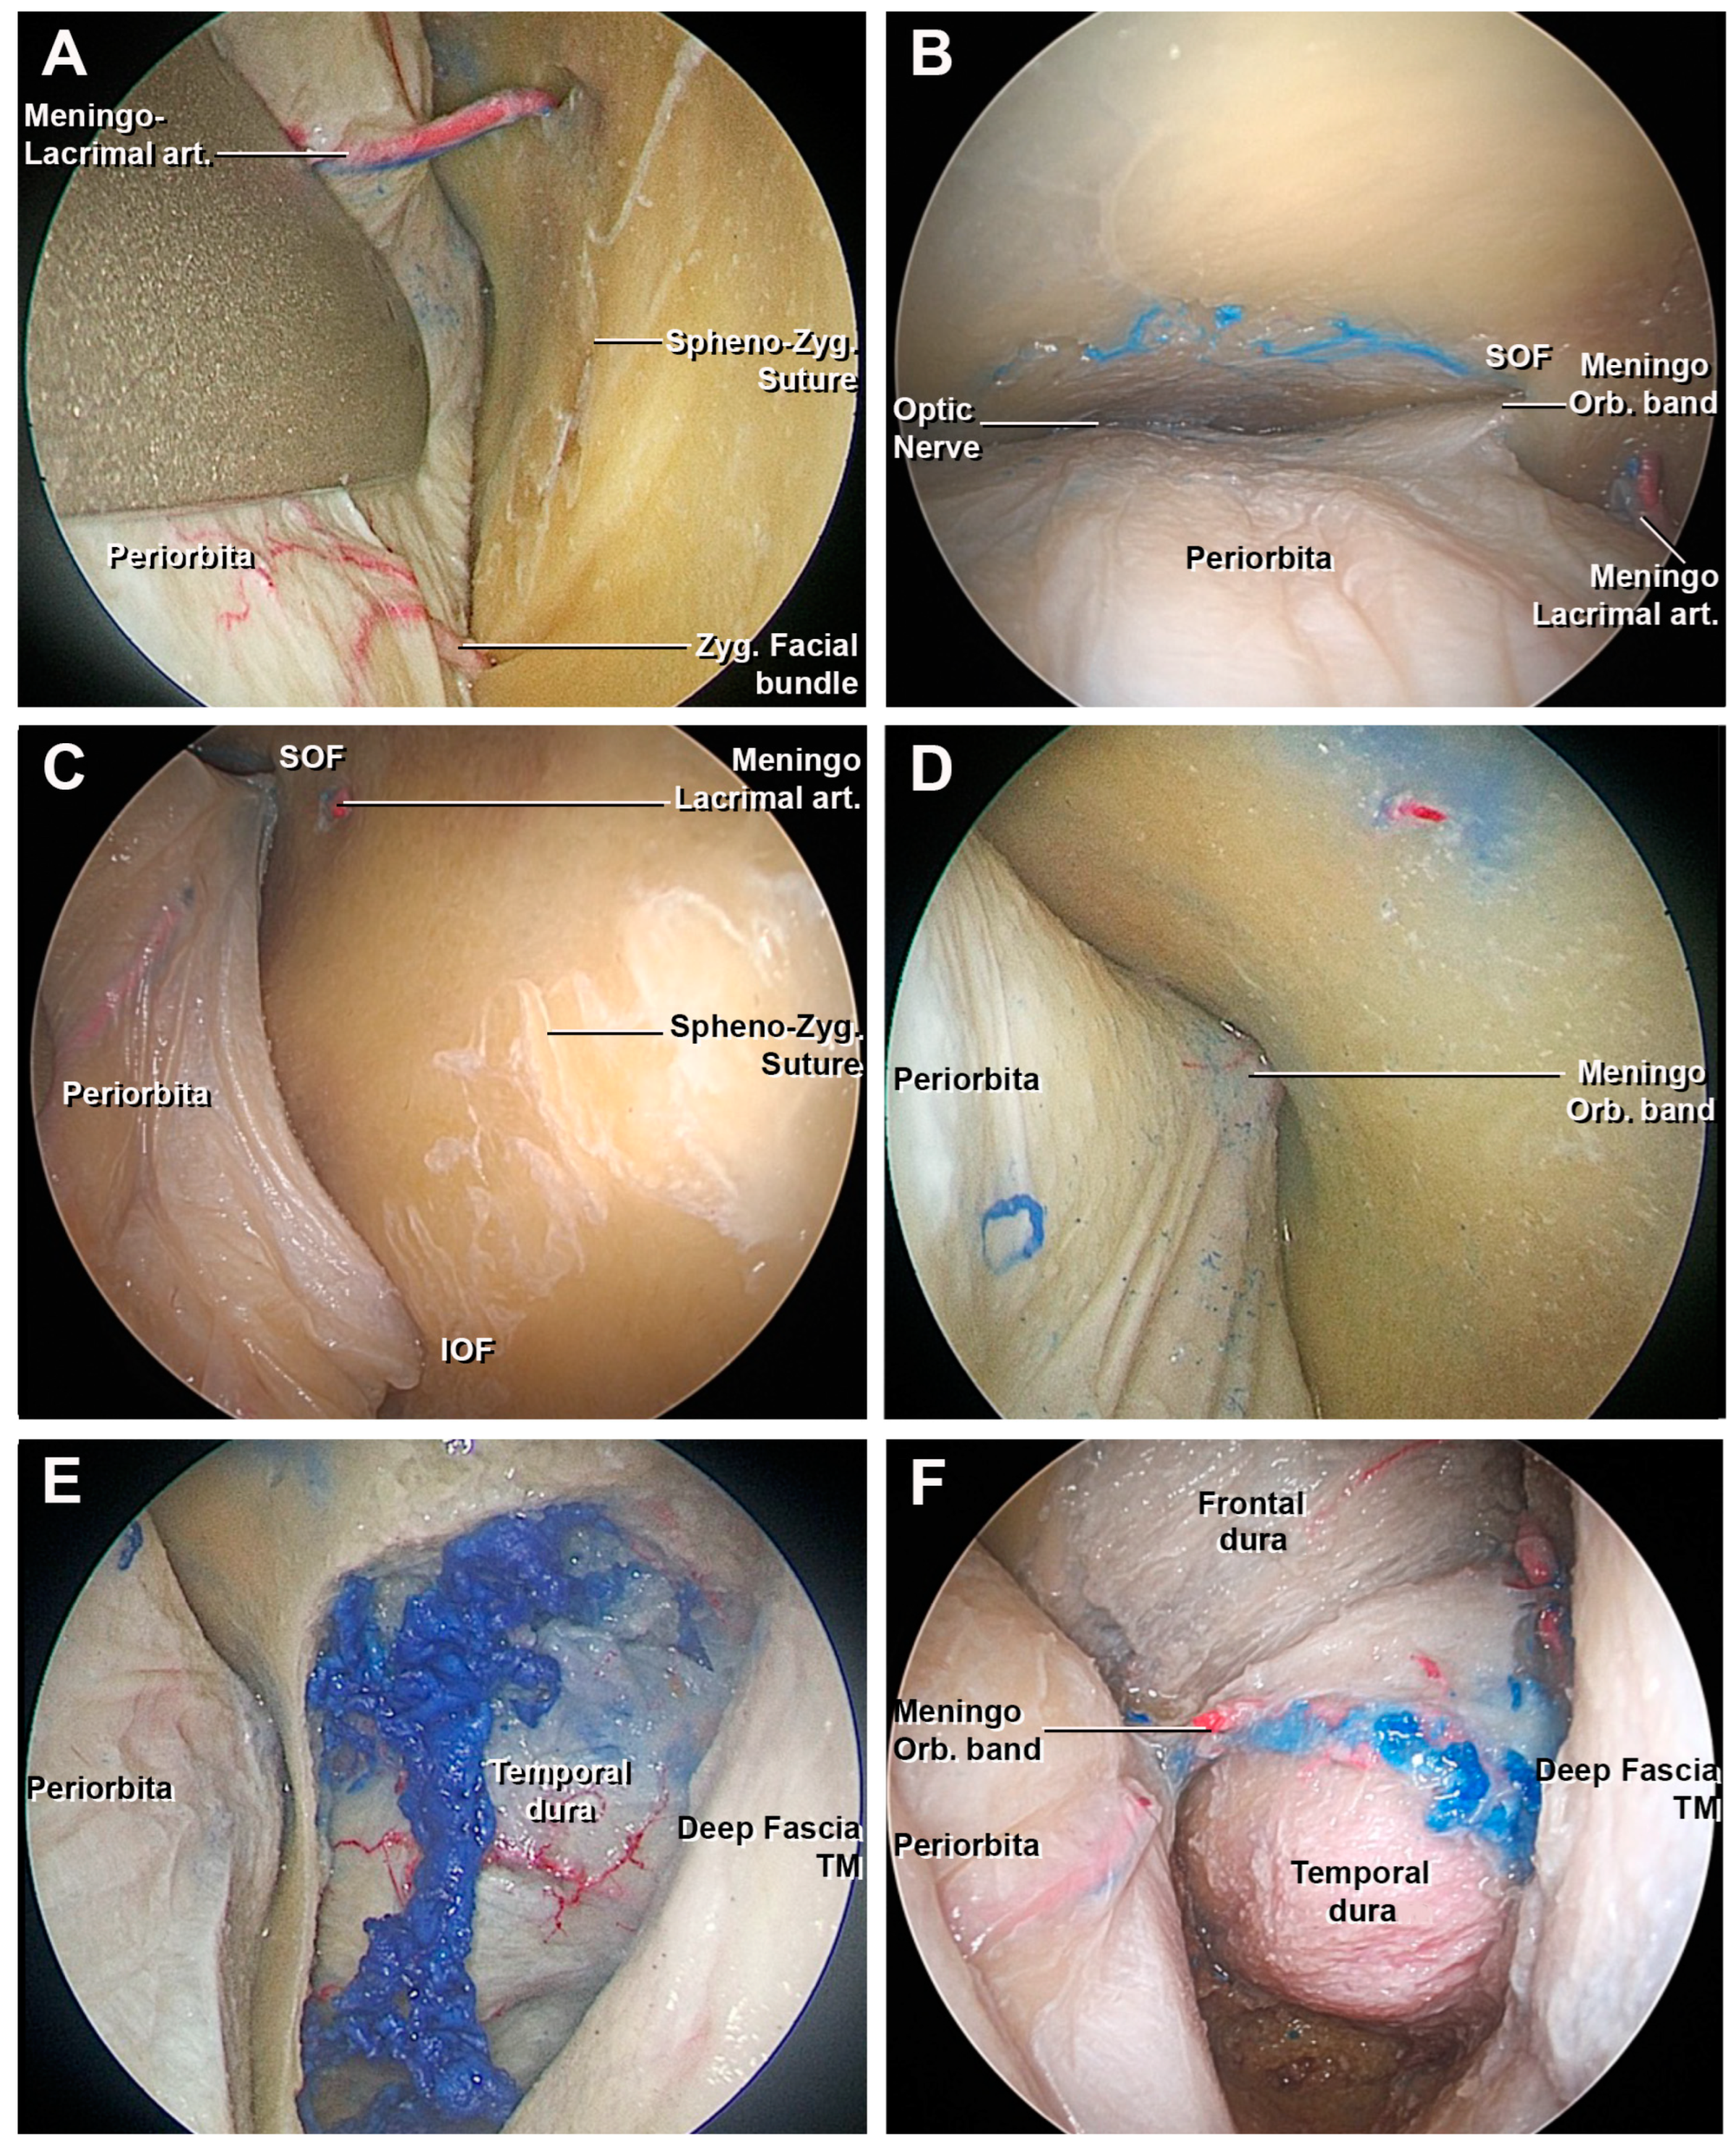

3.1. Step-by-Step Dissection

3.1.1. Craniectomy

3.1.2. Access to the Middle Fossa and Petrous Apex

3.1.3. Access to the Lateral Wall of the Cavernous Sinus and Anterior Clinoidectomy